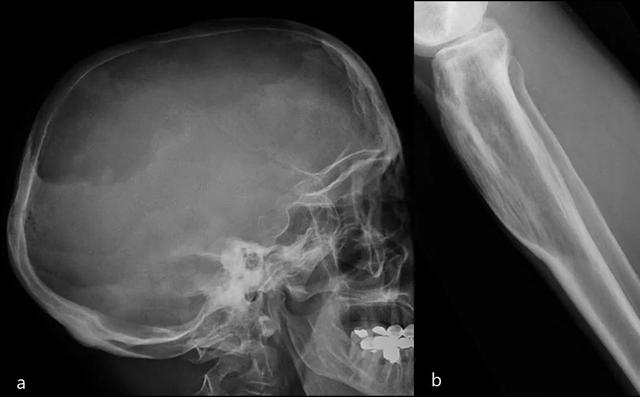

多发性疾病(65%)比单一性疾病更普遍。最常见的受累部位是骨盆,脊柱,头骨和近端长骨。

在头骨中,更常见的发现是剪纸画样的骨质疏松(大,明确的裂解病变),板障扩大和姚蜜昂样形态(混合溶解和硬化病变)。

脊柱:相框标志(包裹椎体边缘的皮质增厚和硬化),椎骨的平方和垂直小梁增厚比骨内血管瘤中看到的模式更粗糙。

长骨:草叶或蜡烛火焰标志:开始作为透明度的软骨下区域,具有V形骨溶解的前端,向骨干延伸。

骨闪烁显示疾病的所有阶段的摄取显着增加(图20)。

图20:患者病程10年。颅骨的侧位X线片(a):颅骨中大的明确的溶解病变,内颅骨表和外颅骨表都涉及(局限性骨质疏松)。胫骨的侧位X线照片(b):具有V形前端的透明度的软骨下区域骨溶解,向骨干延伸。除图像外,血清碱性磷酸酶(ALP)和尿羟脯氨酸升高证实了Paget病在裂解阶段。